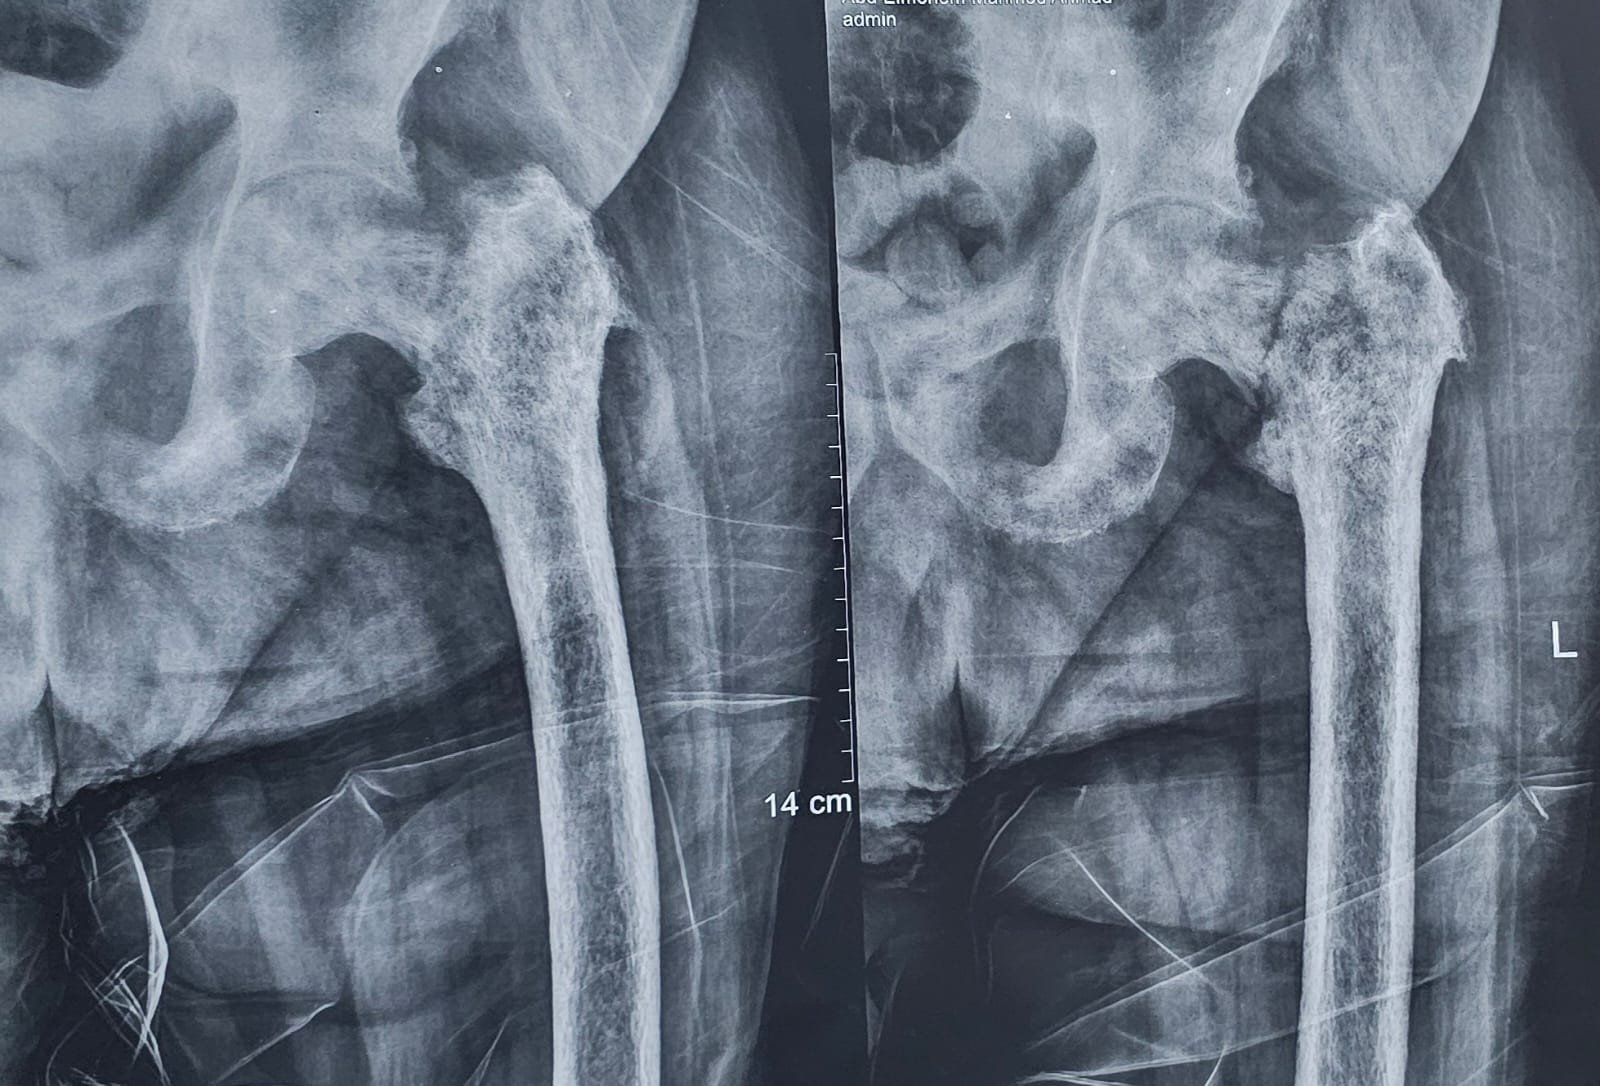

في عمر تجاوز الثمانين، واجه أحد الأبطال تحديًا قاسيًا مع مرض شرس؛ فقد أصيب بسرطان البروستاتا الذي لم يكتفِ بالبقاء في موضعه، بل انتشر في أنحاء متفرقة من الجسم، خاصة العظام، حتى أصاب مفصل الفخذ وتسبب في كسره، مما أفقد المريض القدرة على الحركة.

استغرقت العملية وقتًا حساسًا للغاية، نظرًا لحالة المريض الصحية المعقدة، لكنّ الفريق الطبي نجح في تنفيذ الجراحة بكفاءة عالية، مراعين أعلى معايير الجودة الطبية، وهو ما مكن المريض من الوقوف على قدميه بعد يومين فقط، وبدء مرحلة التعافي تدريجيًا.